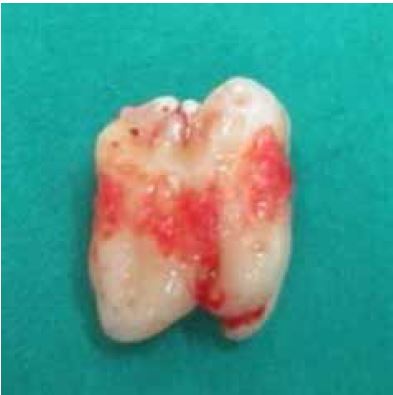

Una vez realizada la avulsión de las piezas (figura 5), se procede al lavado y curetaje del alveolo con Cloruro de Sodio (suero fisiológico) al 0,9% y cureta de alveolo. Finalmente se realizó 5 puntos de sutura simple con hilo seda negra.